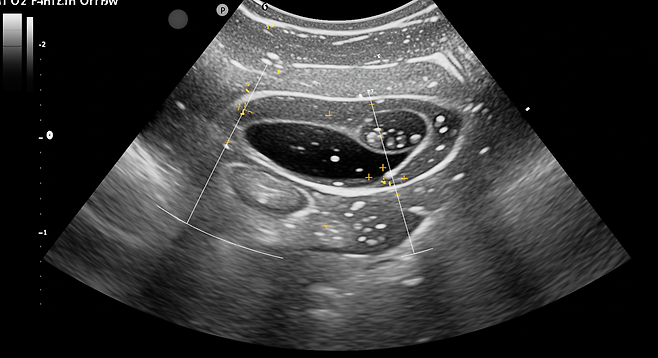

따라서 정기적인 부인과 검진과 초음파 검사가 중요합니다. 특히 40대 이후 여성이라면 이러한 검진을 1~2년마다 받는 것이 권장됩니다.